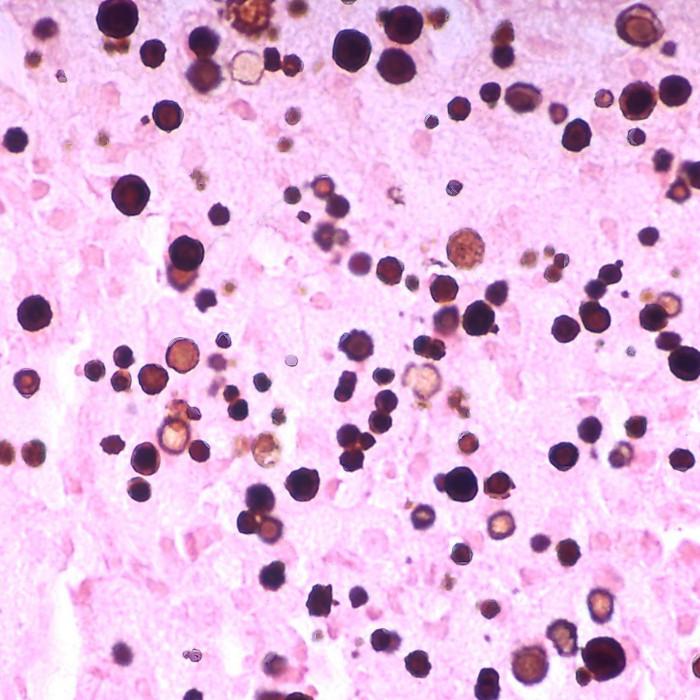

📌 Von Kossa

تستهدف الكالسيوم، النواه، والسايتوبلازم

Calcium الاسود

Nuclei احمر

Cytoplasm وردي